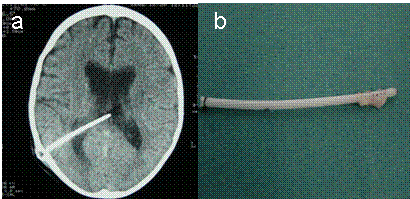

Mekanik sorunlar: Cihazın uygun çalışmasını engelleyen mekanik nedenlerdir. Beyin-omurilik sıvısının içindeki kimyasal maddeler ve beyin dokusu şantı tıkayabilirler. Şanttıkanması olduğunda, kafa içindeki fazla sıvı boşalamayacağı içi tıpkı hidrosefalideki gibi belirtiler görülmeye başlanır. Tıkanma şantın karıncığa takılan bölgesinde, pompa kısmında ya da uç kateter dediğimiz bölümde oluşabilir (Resim 6). Tıkanma nedeni yalnızca doku artıkları ve pıhtılaşmalar değildir; enfeksiyonlara da bağlı tıkanmalar oluşabilir.

Resim 6: (a) BT’de şantın beyin karıncıkları içindeki kateterin tıkanması sonucu yan karıncıkların genişlemesi görülmektedir, (b) yan karıncıktaki kateterin deliklerinin beyin dokusu tarafından tıkandığı görülmektedir.